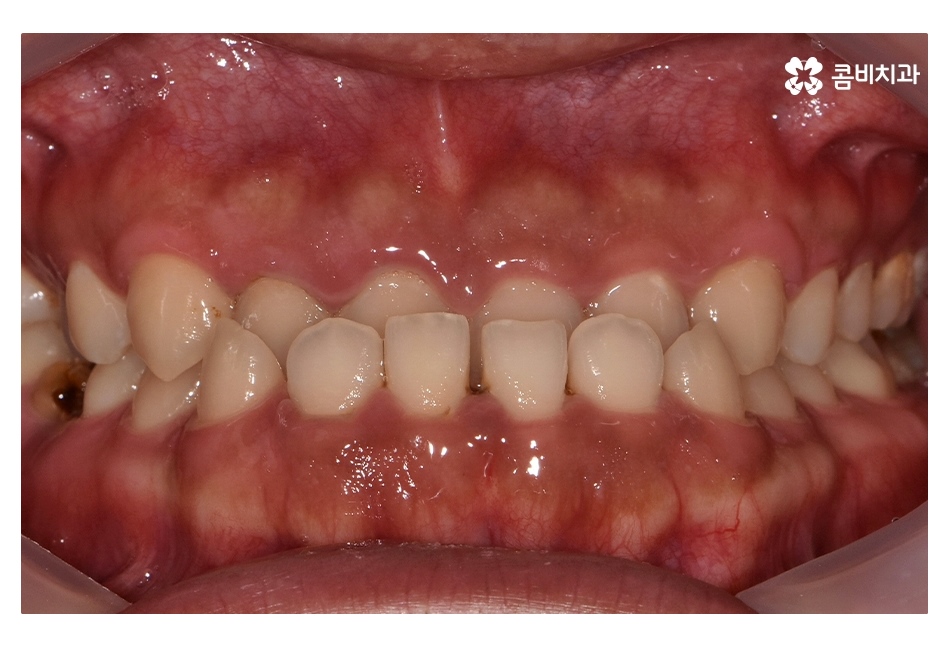

오늘 보시는 사례는 아랫니가 윗니를 덮고 있는

반대교합의 상태로 음식을 제대로 씹지 못하고

발음이 부정확하며 심미적으로도 좋지 않기 때문에

치아교정을 통해 치료가 필요한 케이스 중 하나라고 볼 수 있어요

반대교합은 부정교합 중에 한 종류라고 할 수 있으며

교합이 제대로 맞물리지 않기 때문에

나이가 들수록 소화불량이나 턱관절 장애 등을 겪을 수 있어요.